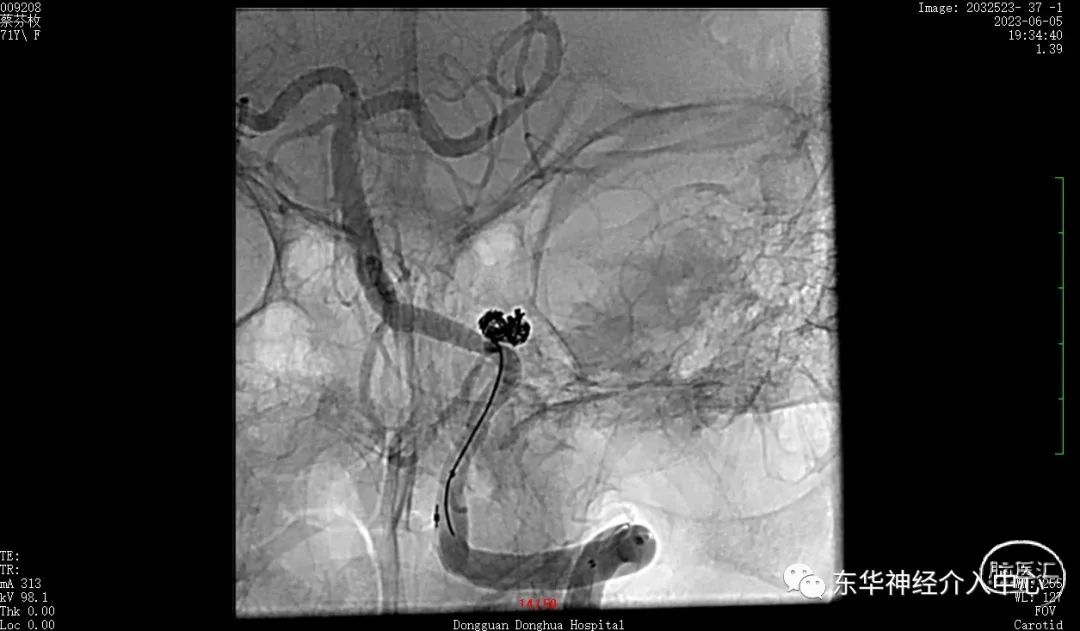

如此信心大增。继续填塞。终于满意的将动脉瘤栓塞,动脉瘤完全不显影。

换一个角度看弹簧圈的形态与动脉瘤的形态基本一致了。

继续换另外一个角度看瘤颈无任何残留。

可见载瘤动脉内微导丝与动脉瘤有间隙,说明动脉瘤成蓝非常满意。